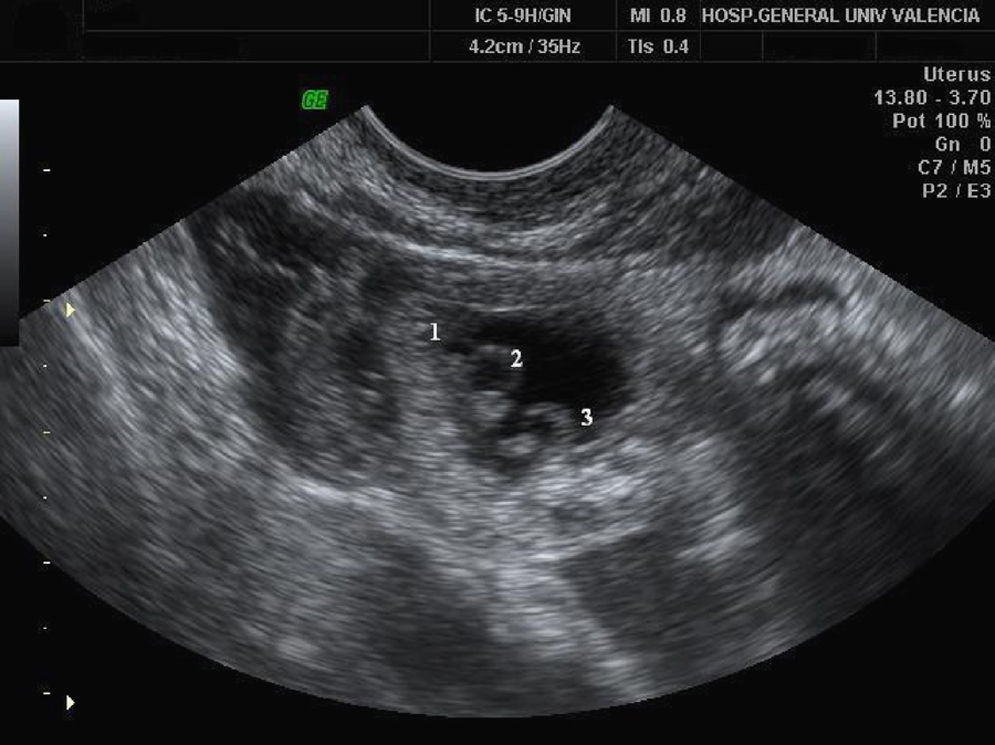

En la ecografía transvaginal se evidenciaron tres vesículas vitelinas con tres polos embrionarios de aproximadamente 3,5mm de LCN y con latidos cardíacos positivos, los tres en un mismo saco enclavado en tercio medio de trompa izquierda (fig. 1). Ambos anejos eran normales. El útero era regular, con la línea endometrial de 7,5mm espesor. En el saco de Douglas había cerca de 25mm de líquido libre (fig. 2).